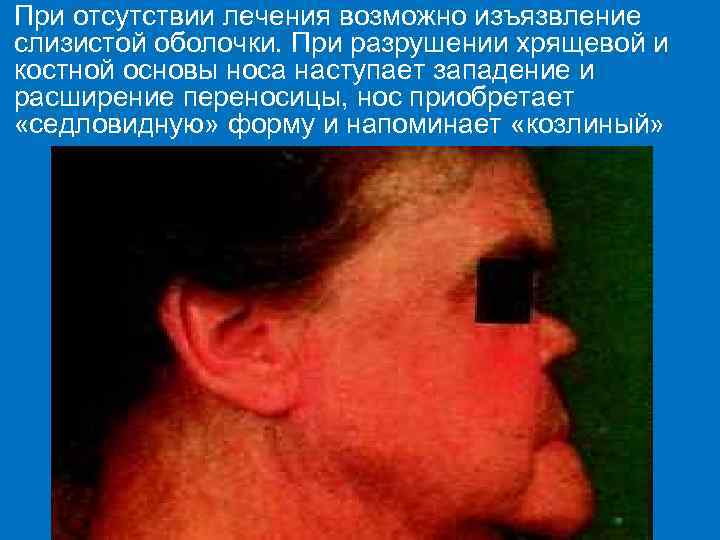

При отсутствии лечения возможно изъязвление слизистой оболочки. При разрушении хрящевой и костной основы носа наступает западение и расширение переносицы, нос приобретает «седловидную» форму и напоминает «козлиный»

Вероятные признаки Рубцы Робинсона–Фурнье – следствие глубоких трещин кожи в области диффузной папулёзной инфильтрации, перенесенной в грудном возрасте. Они представлены тонкими белесоватыми полосками рубцовой ткани, пересекающие красную кайму губ и продолжаю-щиеся на окружающую кожу, особенно в области углов рта. Седловидный или «козлиный» нос – результат разрушения носовой перегородки и хряща при специфическом рините. На слизистой оболочке носа нередко наблюдается характерное хр. поражение в виде озены (зловонный насморк).